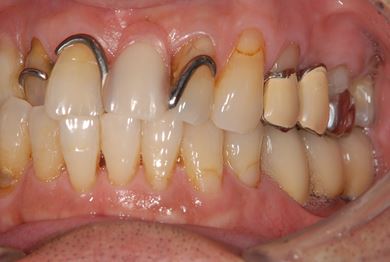

| 性別/年齢 | 男性 / 65歳 | ||||||||||||||||||||||||||||||||

| 主訴 | 右奥歯の義歯の不具合について相談したい。 | ||||||||||||||||||||||||||||||||

| 治療方針 | 抜歯と同時にインプラント埋入を行い、治療期間を短縮する。 | ||||||||||||||||||||||||||||||||

| 治療内容 | インプラント5本(抜歯即日スピードインプラント、テンポラリーインプラント)、メタルボンドセラミッククラウン5本 | ||||||||||||||||||||||||||||||||

| 総治療費 | 1,913,100円 | ||||||||||||||||||||||||||||||||

| 治療期間 | 1年9ヶ月 |